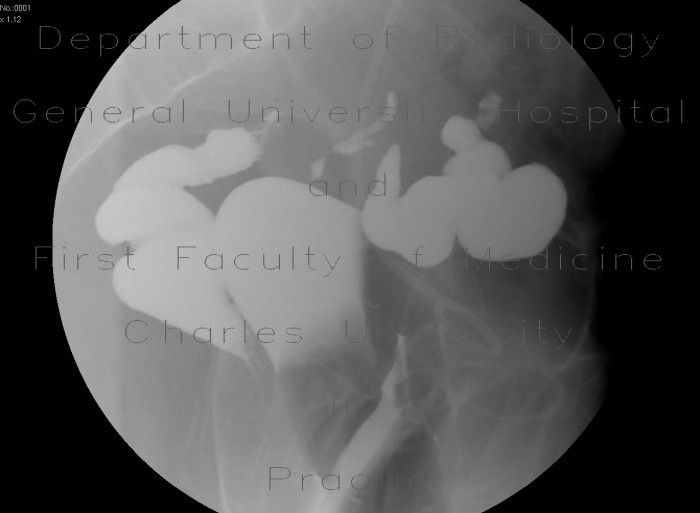

Case Report: Solitary Ischaemic Small bowel stenosis

Case report: Solitary ischaemic small bowel stenosis stenosis in the patient presented here and was confirmed by histological examination. In conclusion, the present case illustrates the need to ... Retrieve Document